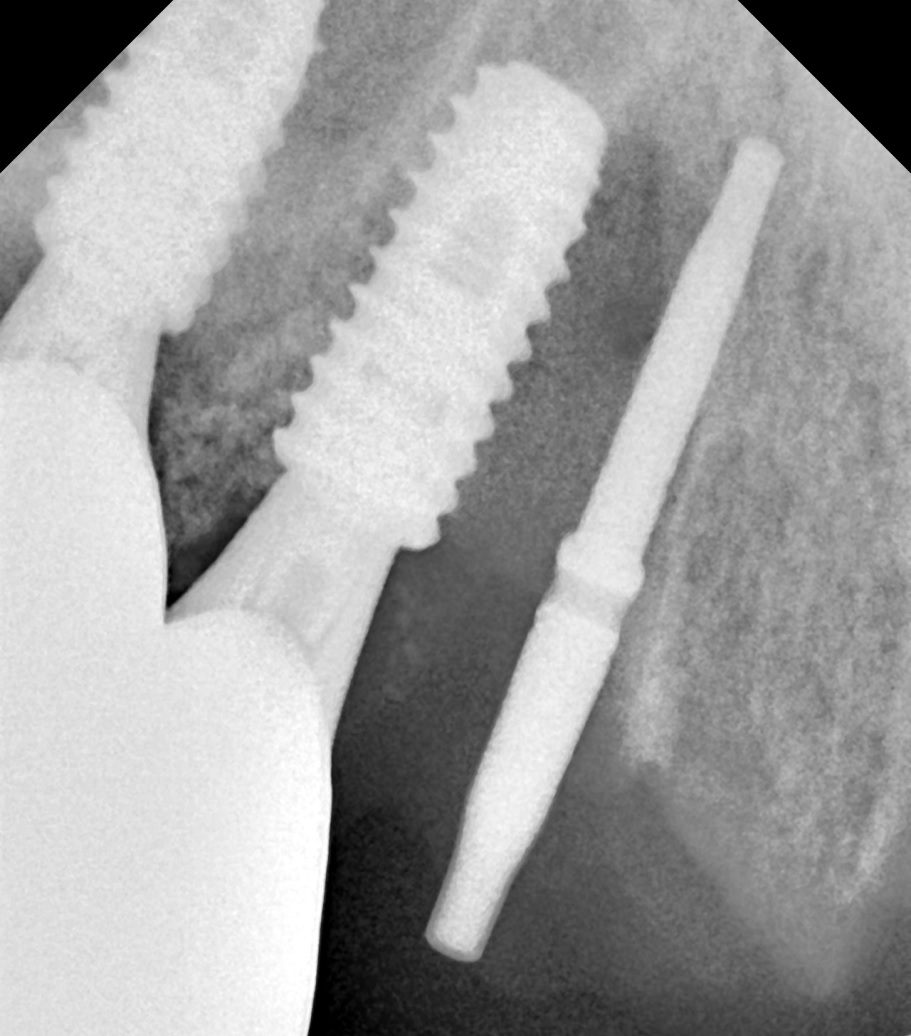

엑스레이 사진상에 위 앞니쪽 모든 치아뿌리 끝에 염증 병소가 보이고, 특히 우측 견치(송곳니)는 심한 우식으로 치관부(머리부분)가 전혀 남아있지 않은 상태였습니다.

해당 치아 3개 모두 발거하고 임플란트 수술 중간중간 방향을 확인하며 수술을 마무리 하였습니다.

치아 뿌리 끝 염증부위에는 모두 골이식을 동반하였으며, 수술 직후 바로 본을 떠서 다음날 아침 일찍 임시치아를 끼워드리기로 계획하였습니다.

임플란트는

덴티움社의 Superline 을 사용했으며 해당 부위 모두 적당한 위치로 식립되었습니다.

모든 임플란트에 연결하여 바로 임시치아를 만들어드리려고 하였으나 우측 송곳니 (사진상 좌측) 에는 치조골 상태가 좋지 않아서 다량의 골이식 및 임플란트를 잇몸 안에 묻어두기로 결정하였습니다.

따라서 가운데 임플란트와 좌측 송곳니 임플란트 (사진상 우측)만 기둥을 연결하여 임플란트 본을 떴습니다.